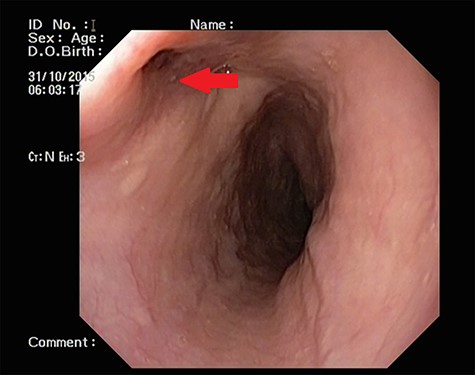

Patient 1: a 52-year-old woman, non-diabetic, non-hypertensive, was referred to the emergency with a history of large-volume, frank hematemesis (four episodes in 3 days). Positive history included recurrent cough for the past 1 year and low-grade fever for 3 months. No history of dysphagia, jaundice, abdominal distension, pain abdomen or altered sensorium. No history of chronic medications (oral anticoagulants or anti-platelets), analgesic intake or any substance abuse. She had received four units of packed red cells at an outside facility prior to admission. She was conscious, oriented, hemodynamically labile (heart rate: 110/min; BP: 86/60 mm Hg) with mild fever (99°F). General survey revealed obvious pallor. All other system examinations were within acceptable limits. Her hemoglobin (Hb) was 7.3 gram%, total leukocyte count (TLC) was 6400 cells/mm3, total bilirubin was 1.31 mg/dl and total protein was 4.75 gram%. An urgent UGI endoscopy revealed an opening in the posterior wall of the lower third of the esophagus, with a diverticulum. Inflammatory changes were noted in the diverticulum (Fig. 1). Contrast-enhanced computed tomogram (CECT) revealed erosion of the pouch into the thoracic aorta (Fig. 2), and a diagnosis of AEF with acute UGI hemorrhage was made.

Patient 2: a 48-year-old hypertensive, non-diabetic gentleman, presented to the emergency with one episode of massive hematemesis. There was no history of dysphagia, jaundice, abdominal distension, pain abdomen or altered sensorium. Past history was significant for percutaneous coronary intervention with two drug-eluting stents performed 3 years ago, for which he was on aspirin. He had normal mentation, his BP was 90/60 mm Hg and his heart rate was 120/min. A general survey revealed pallor and rest of the systemic examination was normal. His Hb was 6.1 gram% and TLC was 6300 cells/mm3. Liver function tests, coagulation parameters, renal function and electrolytes were normal. Chest X-ray was unremarkable. He was initially resuscitated with intravenous fluid, packed red blood cells and a proton-pump inhibitor infusion. An urgent UGI endoscopy revealed a large depressed ulcer with a red spot located in the middle third of the esophagus. A diverticulum was seen in the lower end of the ulcer (Fig. 7). An endoscopic clip was applied to the margin for ease of identification. CECT thorax revealed a 6 cm saccular thoracic aortic aneurysm distal to the left subclavian artery, eroding into the esophagus (Fig. 8).